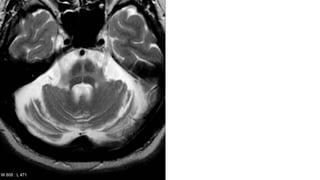

•T2 hyperintensities: typically present in the pontocerebellar tracts

• pons: hot cross bun sign (MSA-C)

•MSA-C

• disproportionate atrophy of the cerebellum and brainstem (especially olivary nuclei and middle

cerebellar peduncle)

RADIOGRAPHIC FEATURES •T2 hyperintensities:typically present in the pontocerebellar tracts • pons: hot cross bun sign (MSA-C) • middle cerebellar peduncles • Cerebellum putaminal findings in MSA-P :  reduced volume  reduced GRE and T2 signal relative to globus pallidus  reduced GRE and T2 signal relative to red nucleus  abnormal disruption of the normal high T2 linear rim., •MSA-C • disproportionate atrophy of the cerebellum and brainstem (especially olivary nuclei and middle cerebellar peduncle)